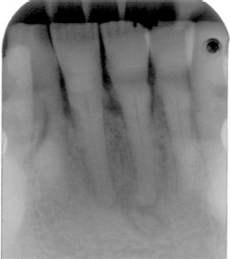

Les zones radiotransparentes indiquent généralement qu’une infection est présente ou qu’il peut y avoir un kyste ou éventuellement une

Figure 1 : Avec l’aimable autorisation du Dr Takashi Komabayashi

tumeur en développement. Le clinicien doit prendre une décision concernant la gravité de la lésion observée. Essentiellement, pendant la phase de développement, la lésion peut ressembler davantage à un kyste. Pendant le stade de calcification, la lésion peut apparaître davantage comme une tumeur selon le degré de calcification.

La dysplasie cémento-osseuse (DCO) est une affection bénigne asymptomatique dont l’étiologie ou la pathogénie est inconnue.

Dans les cas de dysplasie cémento-osseuse, une confusion peut survenir lorsque le clinicien pense que la dent peut nécessiter un traitement de canal ou une extraction sur la base de l’aspect radiographique. Trois variations peuvent se produire dans l’apparence clinique (Komabayashi et Zhu, 2011) telles que :

- Stade précoce (radiotransparence sans inclusion de radiopacité)

- Stade mixte (radiotransparence avec inclusion de radiopacité)

- Stade mature (radiopacité). Ce stade est plus radio-opaque, mais, comme vous pouvez l’imaginer, le degré des apparences radiotransparentes et radio-opaques peut varier considérablement.

Généralement, on soupçonne un état pathologique si une zone radiotransparente mixte ou une lésion opaque est présente. Une investigation diagnostique comprendrait des tests de percussion, de palpation, des tests au froid (glace) et un test pulpaire électrique. La dysplasie cémento-ossifiante périapicale se présenterait avec une pulpe vitale.